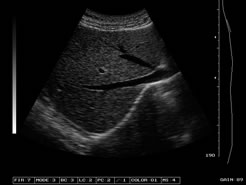

探頭:R6080陣元、3. 5MHz寬頻電子凸陣探頭,自動識別;

變頻:2.5MHz/3.OMHz/3.5MHz/4.0MHz/5.OMHz五種變頻可選;

圖像處理:可變孔徑,動態(tài)變跡、動態(tài)濾波、勾邊增強、數(shù)字時空濾波、8種γ校正、64種以上體位標記、行相關(guān)、幀相關(guān)、點相關(guān)、線性內(nèi)插等;

增益控制:8段TGC、GAIN調(diào)節(jié),總增益連續(xù)可調(diào);